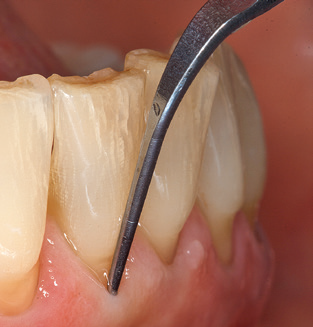

Good illumination of the working field facilitates the process considerably. The system used by the authors achieves this thanks to a 5x LED ring integrated in the handpiece. Naturally, a range of working tips for different indications is also offered. A straight, universally employable tip is the basic instrument required for machine cleaning of natural teeth (Fig. 5a and b). Curved tips, which allow access to exposed furcations, are also available for hard-to-reach areas in the posterior region (Fig. 6).